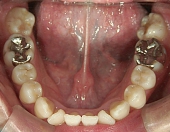

主訴:奥歯で噛んだときに前歯が噛み合わない

高校時代には、歯並びを改善しようと様々な矯正サイトを閲覧し、自分自身が開咬であることを知りました。開咬とは、上下の歯を噛み合わせた時に前歯に隙間ができることを言います。そういえば、麺を前歯で噛みきること、ハンバーガーにガブッと噛みつくことができませんでした。

出っ歯や八重歯などの歯並びの悪さばかりが気になっていましたが、開咬には前歯で物が噛みきれない、しゃべるときに息が漏れるなどの症状の他に、奥歯ばかりに負担がかかる為、歯の寿命を縮めてしまう可能性がありました。矯正で改善することができて本当によかっと思います。みなさんも歯並びで気になることがあったら、気軽に相談してみてくださいね。